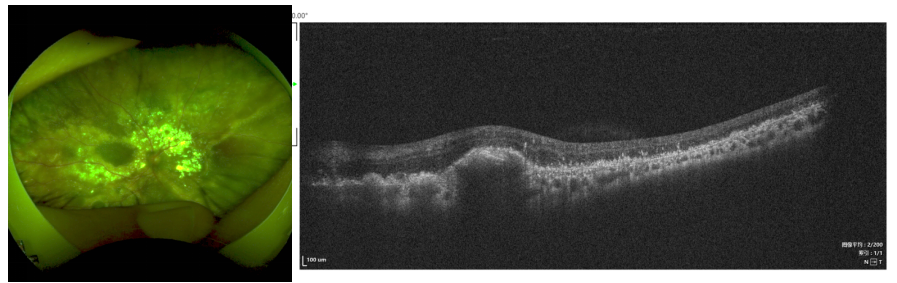

男童,2岁3个月,因体检发现左眼瞳孔呈猫眼状1个月就诊。术前B超检查可见视网膜高度脱离,巩膜外放液术中截屏可见脱离的视网膜贴近晶状体,异常血管清晰可见,背景呈黄色系视网膜下广泛的脂质渗出所致,属于Coats病3B期。本例患儿存在广泛视网膜异常血管并高度脂质性脱离,给予了巩膜外放液联合眼内光凝异常血管手术。联合抗VEGF治疗可以降低异常血管通透性并减轻炎症反应,目前临床上尚无共识,一些小样本临床研究报告首次抗VEGF治疗后6-9个月可发生纤维化甚至牵拉性视网膜脱离,但也有调查显示两者无关。本例患者光凝联合抗VEGF治疗随访2年多,渗出吸收、视网膜复位,无观察到纤维化并发症。

术前B超检查:视网膜全脱离

术中截图:眼表照明下即可看到高度隆起的视网膜及其扩张的异常血管、视网膜下脂质渗出

术后随访:视网膜基本复位,异常血管消失,少量脂质沉着